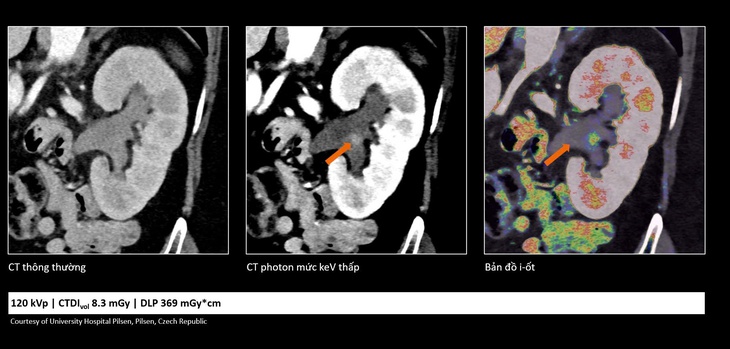

Trong ung thư, việc phát hiện sớm những tổn thương rất nhỏ đóng vai trò quan trọng trong hiệu quả điều trị. Công nghệ cắt lớp vi tính lượng tử cho phép tái tạo hình ảnh với lát cắt rất mỏng (tới 0,2 mm), giúp phát hiện những bất thường mà trước đây có thể bị bỏ sót.

Nhờ đó, bác sĩ có thể nhận diện sớm các dấu hiệu bất thường và đánh giá chính xác hơn đặc tính tổn thương, hỗ trợ hiệu quả trong chẩn đoán sớm cũng như theo dõi tái phát.

So sánh cho thấy công nghệ cắt lớp vi tính lượng tử không chỉ giúp hình ảnh rõ hơn mà còn cung cấp thêm thông tin, hỗ trợ bác sĩ đánh giá tổn thương chính xác hơn - Ảnh: DNCC

Bên cạnh khả năng cải thiện chất lượng hình ảnh, công nghệ cắt lớp vi tính lượng tử còn giúp giảm đáng kể liều tia X và lượng thuốc cản quang sử dụng. Điều này góp phần tăng mức độ an toàn cho người bệnh, đặc biệt với những người có nguy cơ suy thận hoặc mắc bệnh lý nền phức tạp.